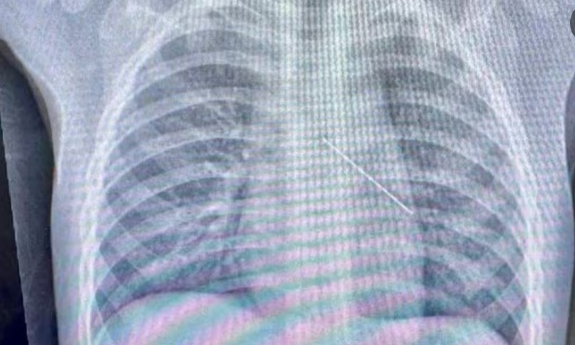

KHẢO SÁT TỶ LỆ NHIỂM MỘT SỐ VI KHUẨN ĐƯỢC PHÂN LẬP TỪ MẪU BỆNH PHẨM ĐỜM CỦA NGƯỜI BỆNH VIÊM PHỔI TẠI BỆNH VIỆN ĐA KHOA ĐỨC GIANG NĂM 2024 VÀ CÁC YẾU TỐ LIÊN QUAN

KHẢO SÁT TỶ LỆ NHIỂM MỘT SỐ VI KHUẨN ĐƯỢC PHÂN LẬP TỪ MẪU BỆNH PHẨM ĐỜM CỦA NGƯỜI BỆNH VIÊM PHỔI TẠI BỆNH VIỆN ĐA KHOA ĐỨC GIANG NĂM 2024 VÀ CÁC YẾU TỐ LIÊN QUAN Xác định chính xác tác nhân gây bệnh là chìa khóa để xây dựng phác đồ kháng sinh hiệu quả, đặc biệt trong bối cảnh... 29/03/2026 17:20 Nghiên cứu khoa học